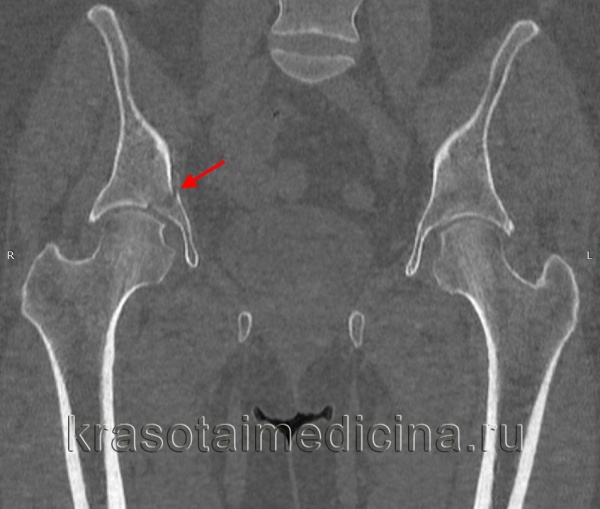

Межвертельные переломы являются внекапсульными и проходят через губчатую кость между большим и малым вертелами. Они обычно встречаются у пожилых больных в возрасте от 66 до 76 лет, у женщин в 4—6 раз чаще, чем у мужчин. Кровоснабжение этой области очень хорошее благодаря тесному прилеганию окружающей мускулатуры и наличию губчатой кости.

Внутренние ротаторы бедра остаются прикрепленными к проксимальному фрагменту, в то время как короткие наружные ротаторы остаются прикрепленными дистальнее головки. Классификацией Boyd и Griffin пользуются большинство ортопедов, однако врачам неотложной помощи достаточно классифицировать эти переломы только на стабильные (I тип) и нестабильные (II тип).

Класс В, I тип: стабильные межвертельные переломы. Единичная линия перелома пересекает кортикальный слой между двумя вертелами. Между диафизом и шейкой бедренной кости смещения нет. Класс В, II тип: нестабильные межвертельные переломы. Между диафизом и шейкой бедра имеется несколько линий перелома или фрагментация с сопутствующим смещением.

Для выявления этих переломов обычно достаточно снимков в прямой и боковой проекциях.